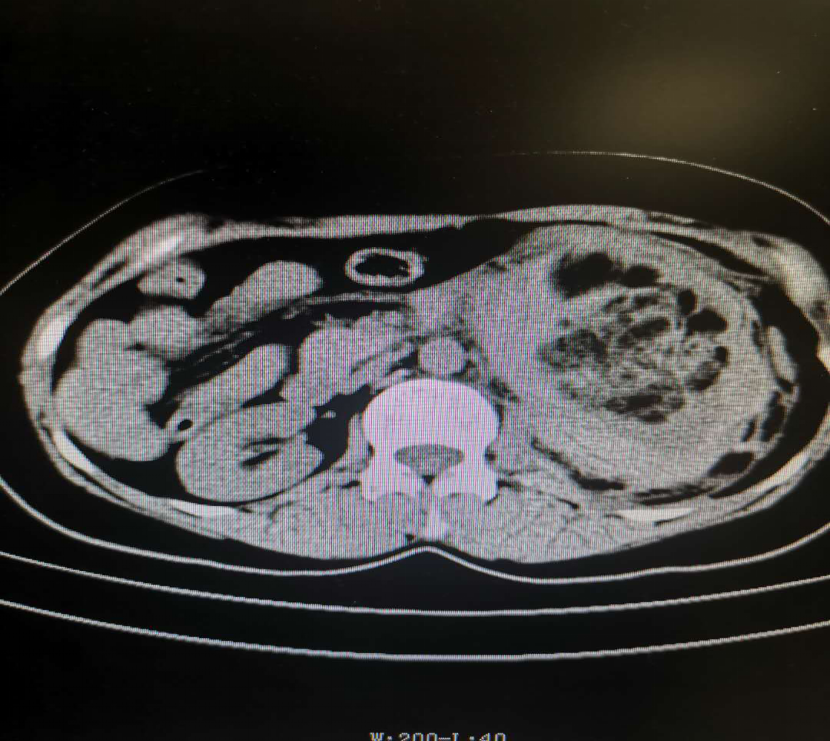

左肾钙化巨大肿块 血管平滑肌脂肪瘤 脂肪瘤 肾癌 病例中心 诊疗助手 爱爱医医学网

肾脏错构瘤破裂出血介入治疗 肾错构瘤 症状 介入治疗